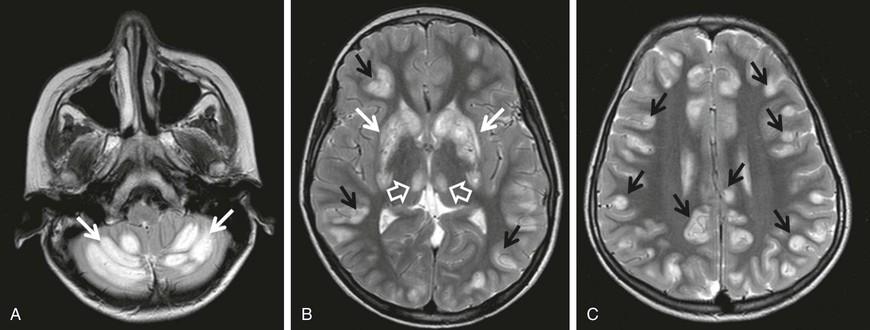

Biotin-responsive basal ganglia disease manifests with episodes of acute dystonia, external ophthalmoplegia and encephalopathy. SLC19A3 is the responsible mutated gene. MRI demonstrates involvement of the basal ganglia, with vasogenic edema and the “bat-wing” sign (Fig. 597-2). Treatment with biotin and thiamine results in improvement in 2-4 days.